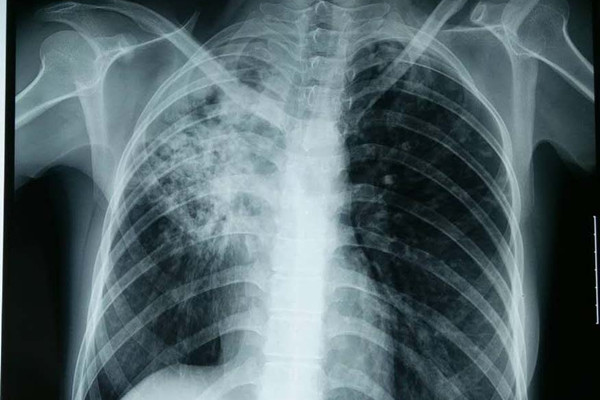

结核性胸膜炎是指结核杆菌与其自溶、代谢产物进人超敏感机体引发的胸膜炎症。发病患者常伴有局部症状如呼吸困难、胸痛、干咳,全身中毒症状有发热、消瘦、盗汗、没食欲等。对于该病如果早期不加以治疗,很有可能会导致胸膜增厚粘连出现。那么早期治疗都有哪些方法呢?